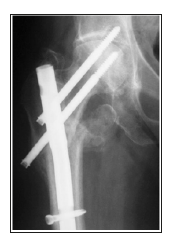

Follow up: Tablet Risedronate 35mg once weekly for 12weeks were given to improve the bone mineral density in patients with severe degree osteoporosis. All the patients were advised to completely weight bearing after 10-12 weeks of post-operative period. All patients were followed up at the end of 1,2,6,12 and 18 months. At each follow up, the radiographs of upper femur and hip were taken to assess the fracture union and the complications. The functional results were calculated according to Harris hip score. All patients enrolled in the study were offered with surgical implant removal at an average of 18months post-surgical procedure who showed the clinical and the radiological union of fractures and improved functional quality of life (Figures 5 & 6).

Figure 6:Subtrochanteric fracture fixed with proximal femoral nail.